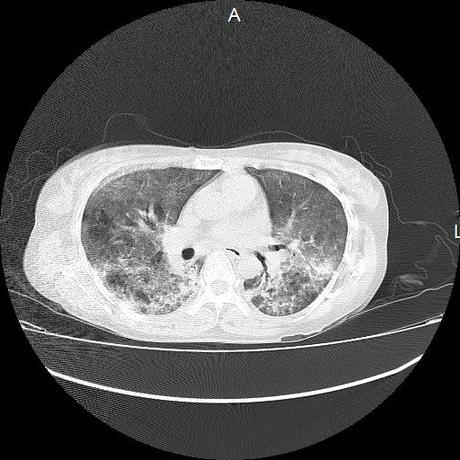

El parénquima pulmonar con areas parcheadas difusas en vidrio despulido combinadas con otras areas hipodensas de baja atenuación debidas a atrapamiento aéreo y engrosamiento intersticial y zonas de fibrosis de predominio en lóbulos medios e inferiores de ambos pulmones.

- LOS HALLAZGOS PUEDEN ESTAR EN RELACIÓN A NEUMOPATIA INTERSTICIAL PROBABLE ETIOLOGIA HIPERSENSITIVA VS AUTOINMUNE/BACTERIANA/FUNGICA.